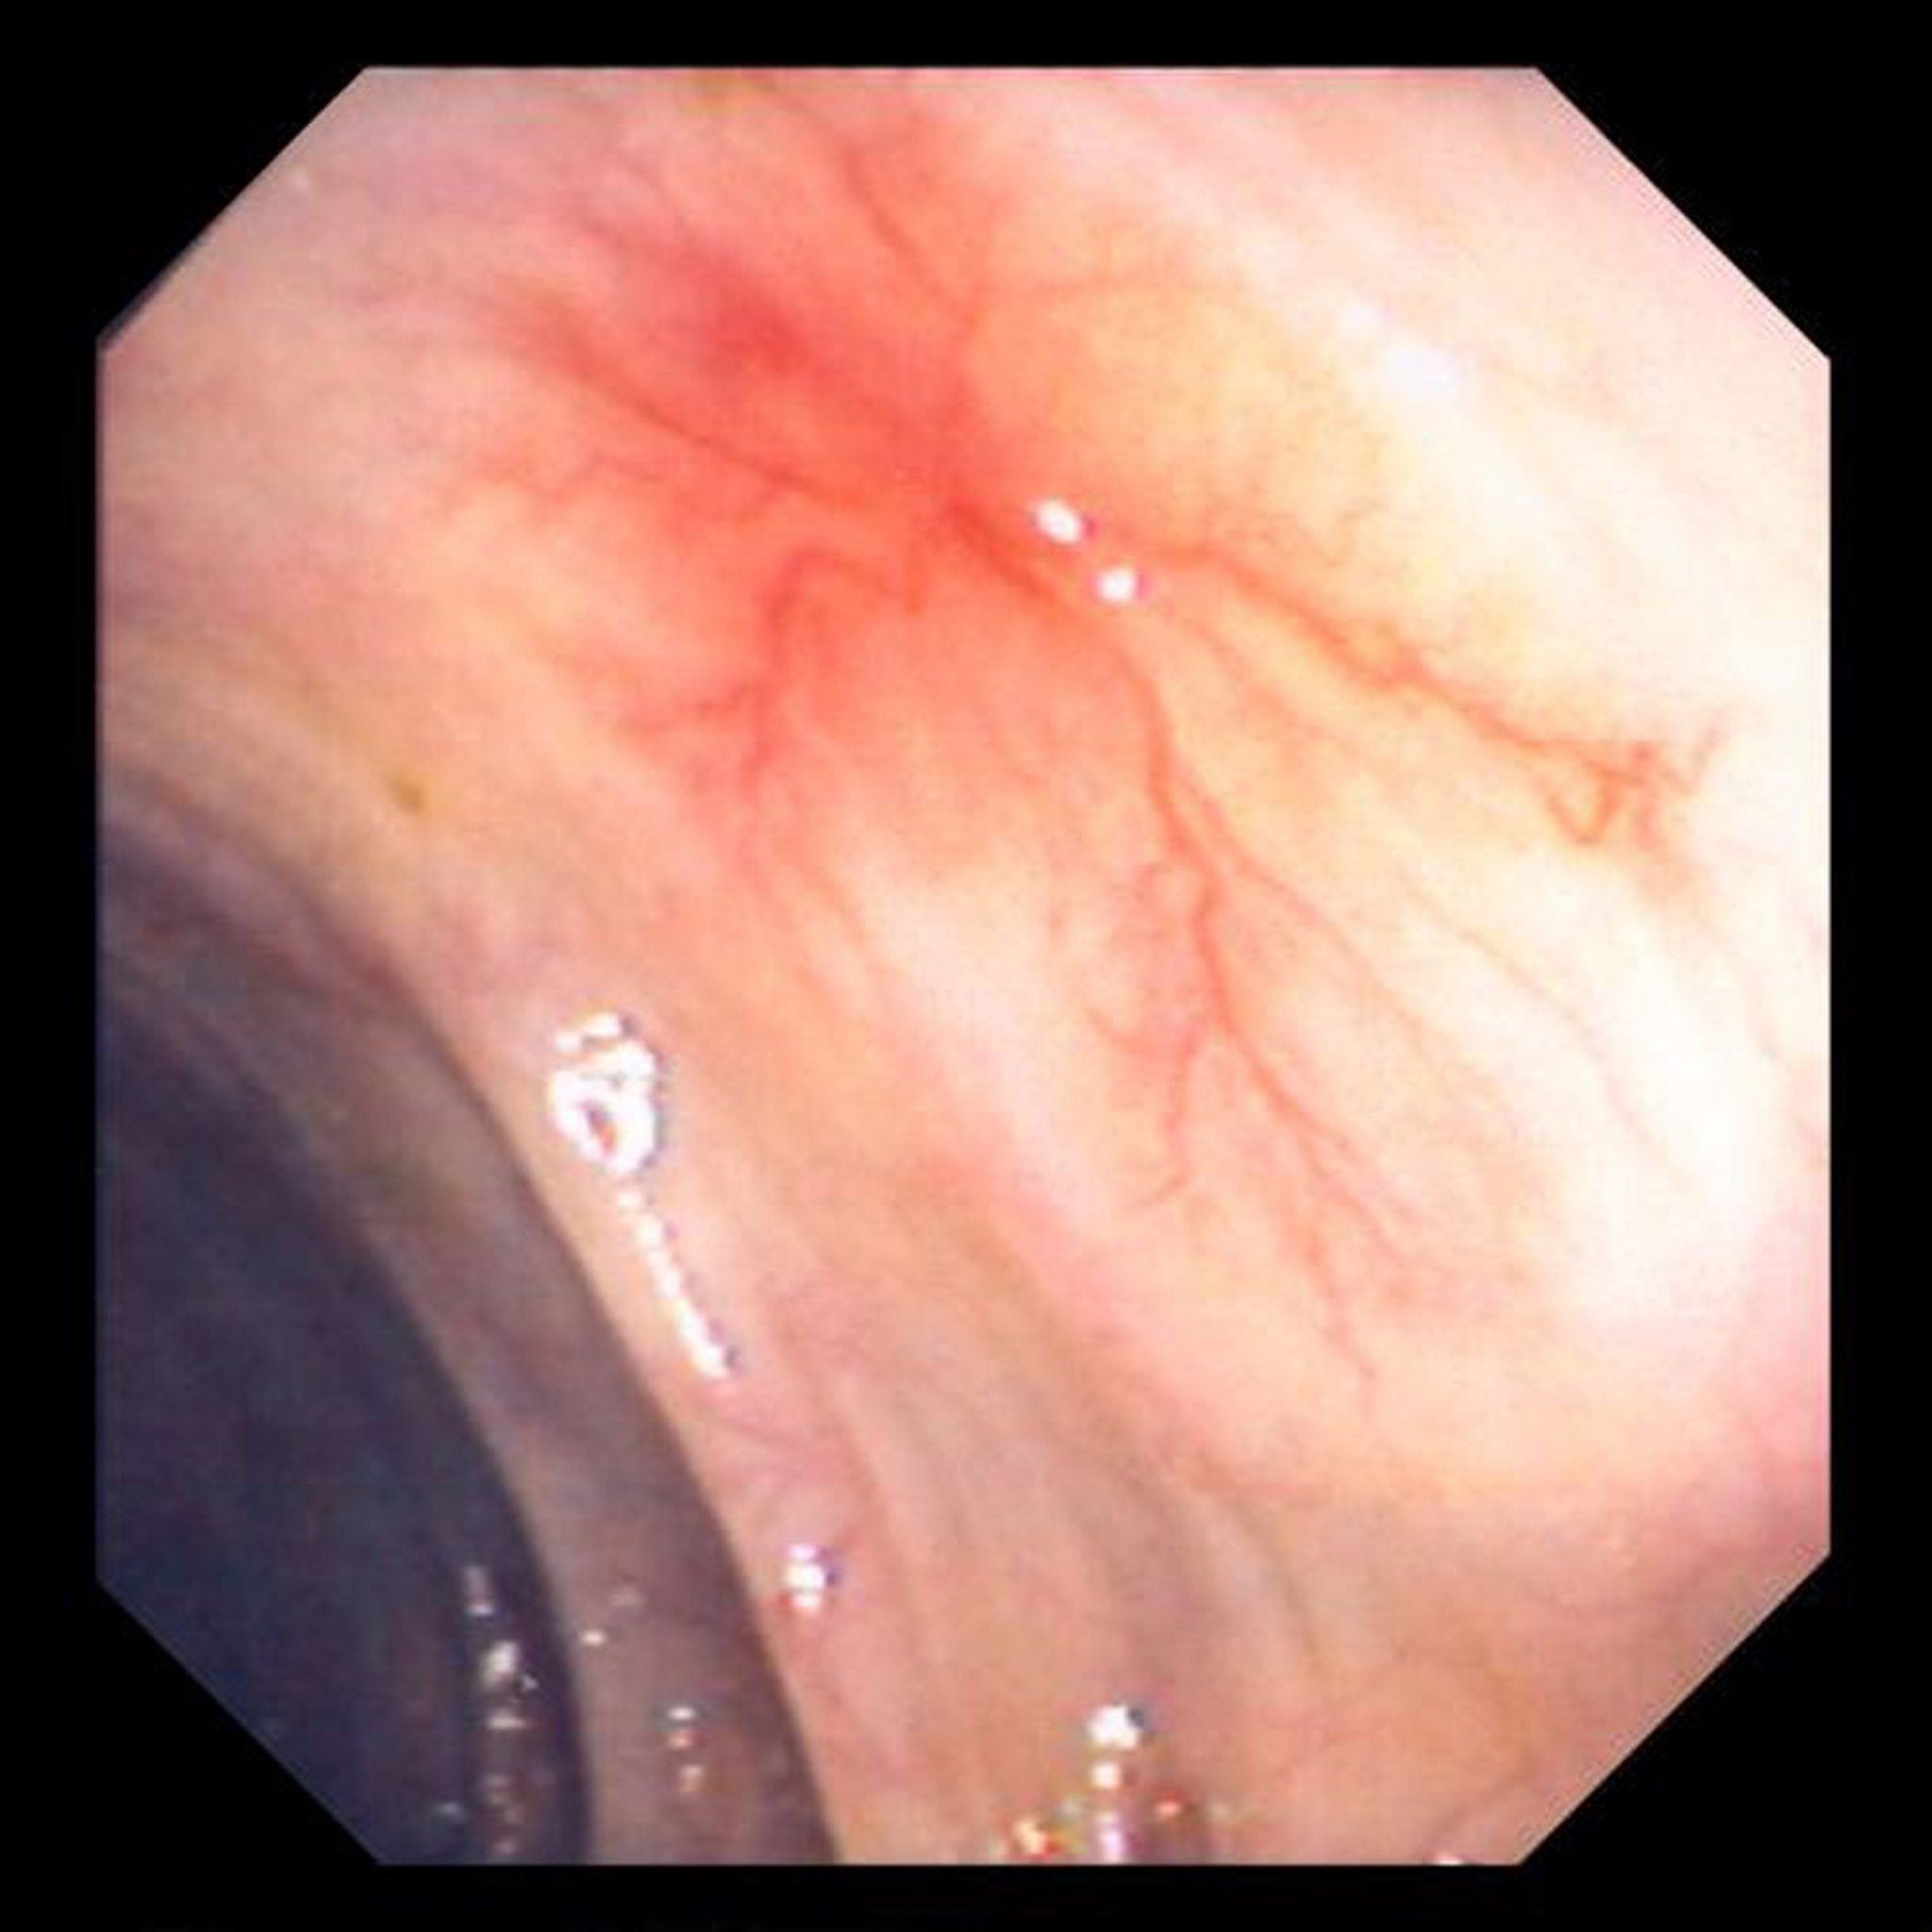

Anomalies vasculaires (angiodysplasie) dans l’intestin

Cette photo montre un vaisseau sanguin anormal dans la paroi de l’intestin.

Image fournie par le Dr David M. Martin.